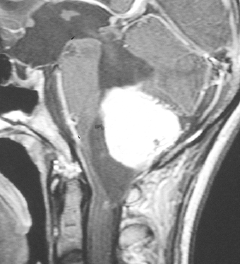

ものすごく難しい血管芽腫

これも血管芽腫です。おそらく小脳発生なのでしょうが,延髄の両側に強く癒着していて延髄の血管も腫瘍の中に入っていて,腫瘍血管には動脈瘤も合併していて破裂しました。この腫瘍を摘出するのは不可能にも思えましたが,無事にできました(下の写真)。患者さんも私もへとへとになりました。 でも,このような血管芽腫の手術はうまく行くとは限りません,手術不可能と考えた方がいいかもしれないと今でも思っています。手術すると決めればものすごく高いリスクを患者さんも外科医も背負うことになります。放射線治療をして治るサイズではないので他に治療法はありませんが (>_<) 大きな血管芽腫を手術する提案をされたら,少なくとも執刀医の経験数は尋ねましょう。